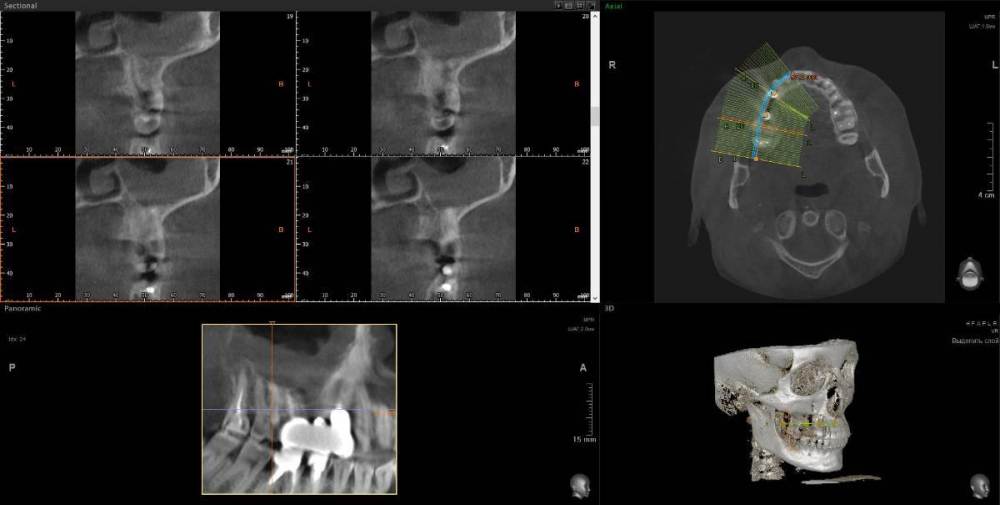

1. Из-за сильного воспаления верхнего зуба костная кость растворилась и дошло до пазух носа. Зуб рекомендуют удалить

2. Импланты установила 2 года назад, в итоге заплачено было 200 тыс. с учетом циркониевых коронок. На КТ обнаружилось сильное воспаление, как следствие растворилась костная ткань импланты, доктор сказал уже не спасти.

Буду очень признательна за консультацию - действительно ли нужно удалять зуб и импланты? КТ во вложении

IMHO. Зуб 18 стоит удалить, зуб 17 стоит полечить. Имплантат в позиции 16, похоже, придётся удалить, имплантат в позиции 14, на мой взгляд, вне опасности.